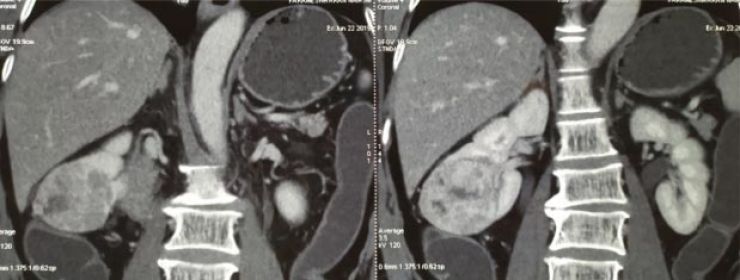

Bướu thận phải giai đoạn T1b đã được các bác sĩ Việt Nam phẫu thuật thị phạm cắt bướu bảo tồn thận